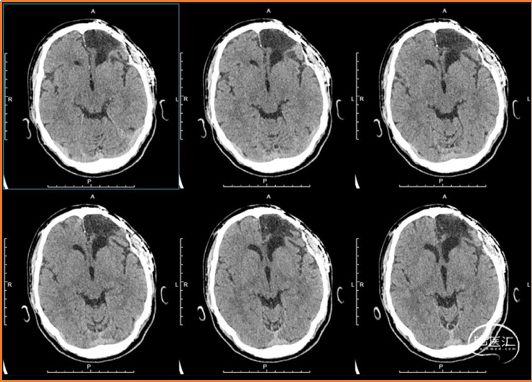

术前检查

术前诊断

1. 脑外伤后遗症,癫痫。

2. 颅骨修补材料凹陷。